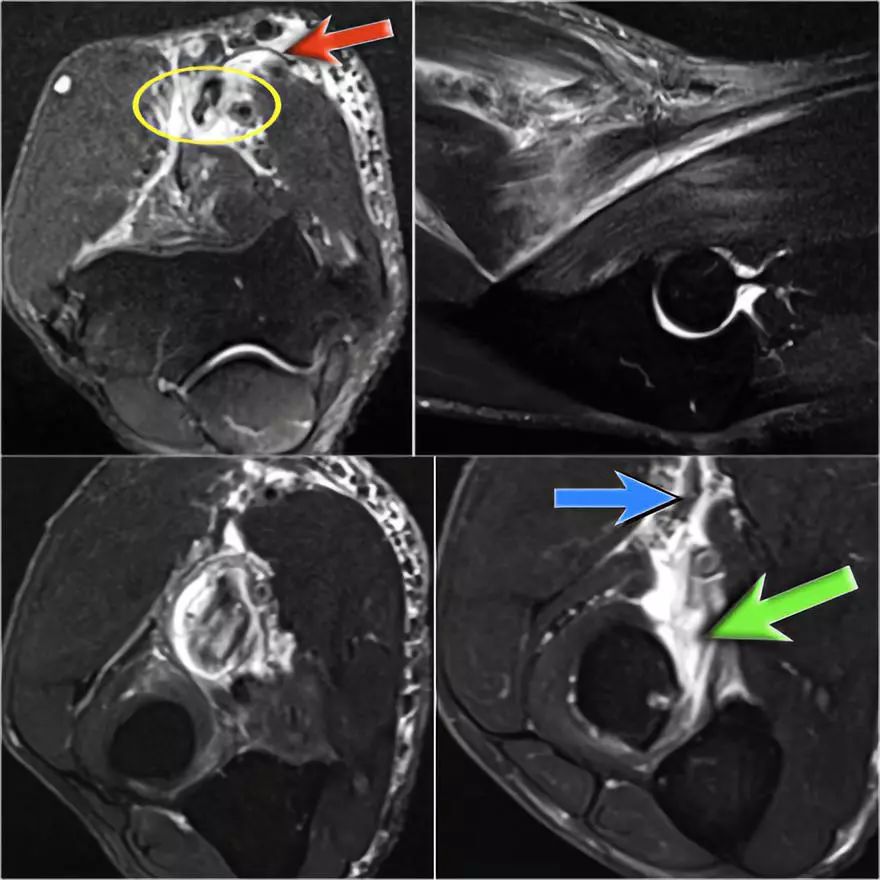

下图是20岁棒球投手的图像。

冠状图像上有一个美丽的UCL前束,但注意到关节内侧部分有骨赘形成(红色箭头)。当我们按照顺序向下看,可以看到存在一小部分低信号强度(黄色箭头),这是UCL的一部分撕裂。

这是在X线片可以更好地观察(黄箭头 )。

当我们看轴向扫描时,我们可以欣赏巨大的骨赘形成。请注意,尺骨神经(蓝色箭头)紧邻这些骨赘,这些可能指示尺神经出现病变。